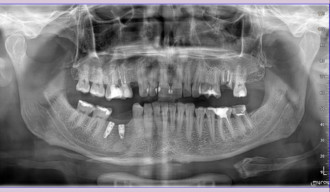

Wskazaniem po takiego leczenia są sytuacje, w których pojawiły się zmiany w okolicy wierzchołków korzeni lub podczas pierwszego leczenia kanałowego kanały zęba zostały opracowane i wypełnione w sposób nieprawidłowy – najczęściej nie zostały dopełnione do wierzchołka korzenia zęba. Obydwa przypadki można zdiagnozować na podstawie analizy obrazu radiologicznego.

Leczenie endodontyczne w Naszym Gabinecie odbywa się tylko i wyłącznie przy użyciu mikroskopu. Tylko odpowiednie powiększenie oraz doświadczenie lekarza pozwala na osiągnięcie odpowiedniego efektu ponownego leczenia kanałowego. Nasz specjalista Dr Mariusz Pietrzak wykonuje takie leczenie podczas jednego spotkania. Macie Państwo, zatem komfort nie tylko bezbolesnego leczenia, ponieważ zawsze odbywa się ono w znieczuleniu miejscowym, ale także kompleksowości ( na miejscu wykonujemy całą diagnostykę radiologiczną ) oraz sprawności leczenia, które można zakończyć podczas jednego spotkania.